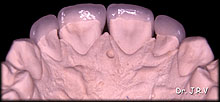

| Foto 1A.- Vista oclusal de carillas de 14 a 24 en modelo maestro. |

Foto 1B.- Vista frontal de carillas de 14 a 24 en modelo maestro. |